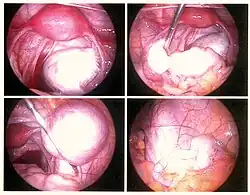

Laparoskopie, chirurgický zákrok, kdy se k nahlédnutí do břišní dutiny používá kamera, je jediným způsobem, jak přesně diagnostikovat rozsah a závažnost pánevní či břišní endometriózy. Laparoskopie není vhodná pro extrapelvická místa, jako je pupek, kýlní vaky, břišní stěna, plíce nebo ledviny.[57]

Laparoskopie umožňuje vizualizaci ložisek v případech, kdy léze není viditelná zvenčí (např. endometriotický uzel ve vagíně) a není lokalizovaná mimobřišně.[57] Pokud nejsou léze viditelné, je nutné ke stanovení diagnózy provést biopsii.[58] Během diagnostické laparoskopie je možné současně provést chirurgickou léčbu endometriózy.

Léze identifikované při laparoskopii se liší velikostí[59] a mohou se jevit jako tmavě modrá, pudrově černá, červená, bílá, žlutá, hnědá nebo nepigmentovaná ložiska. Některé léze ve stěnách pánve nemusejí být viditelné, endometrióza se prokázala při biopsii normálně vypadající pobřišnice u neplodných žen v 6–13 % případů.[60] Časná endometrióza se typicky vyskytuje na povrchu orgánů v pánevní a nitrobřišní oblasti. Větší ložiska se mohou nacházet na vaječnících jako endometriomy nebo "čokoládové cysty", protože obsahují hustou nahnědlou tekutinu, většinou starou krev.[59]

Laparoskopie nebo otevřená operace

Metodou první volby chirurgické léčby je laparoskopie. Při laparoskopické operaci se do těla zavádějí malé nástroje sloužící k odstranění ložisek endometriózy a případných srůstů. Protože jsou řezy velmi malé, po zákroku zůstanou na kůži jen malé jizvičky a většina pacientek se po operaci rychle zotaví a má minimální riziko vzniku pooperačních srůstů.[70]

Vzhledem k rozsahu endometriózy a lokalizaci ložisek, je však v některých případech nutná otevřená operace. Při obou metodách se ložiska endometriózy odstraňují v celkové anestezii za použití tepla (např. laseru). Současně se mohou odstranit případné endometriální cysty nebo uvolnit tkáňové srůsty.[66]